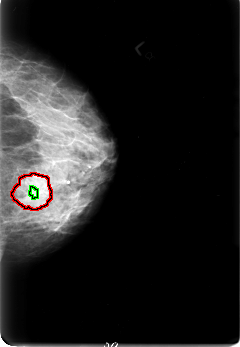

FILE: B_3034_1.LEFT_CC.OVERLAY

TOTAL_ABNORMALITIES 2

ABNORMALITY 1

LESION_TYPE MASS SHAPE LOBULATED MARGINS OBSCURED-ILL_DEFINED

ASSESSMENT 4

SUBTLETY 3

PATHOLOGY MALIGNANT

TOTAL_OUTLINES 1

BOUNDARY

ABNORMALITY 2

LESION_TYPE CALCIFICATION TYPE PUNCTATE-PLEOMORPHIC DISTRIBUTION CLUSTERED

ASSESSMENT 3

SUBTLETY 2